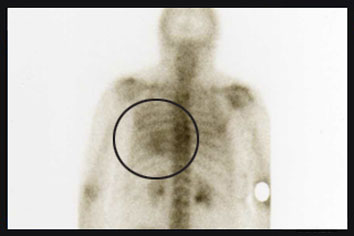

„2012 unterzog ich mich einer Prothesenoperation, sechs Monate später wurde mit einer Szintigraphie das Ergebnis überprüft. Bei der Auswertung der Bilder hat der Arzt eine Veränderung im Bereich des Brustkorbs festgestellt. Die anschließende Untersuchung nach der Bioresonanzmethode führte zur gleichen Diagnose.“

In der Tat zeigen die nuklearmedizinischen Bilder eine krankhafte Veränderung auf Höhe des Brustfells im oberen Brustkorbbereich auf. Zur Bestätigung sowie zur genauen Diagnose der Erkrankung wird sich diese Patientin weiteren radiologischen Untersuchungen unterziehen müssen.

Die Untersuchung nach der Bioresonanzmethode Metatron brachte Störungen im gleichen Brustkorbbereich zutage wie die Szintigraphie. Die Übereinstimmung der Ergebnisse belegt, dass die Bioresonanzmethode eine zuverlässige Technik ist, um Störungen im menschlichen Körper zu erkennen.